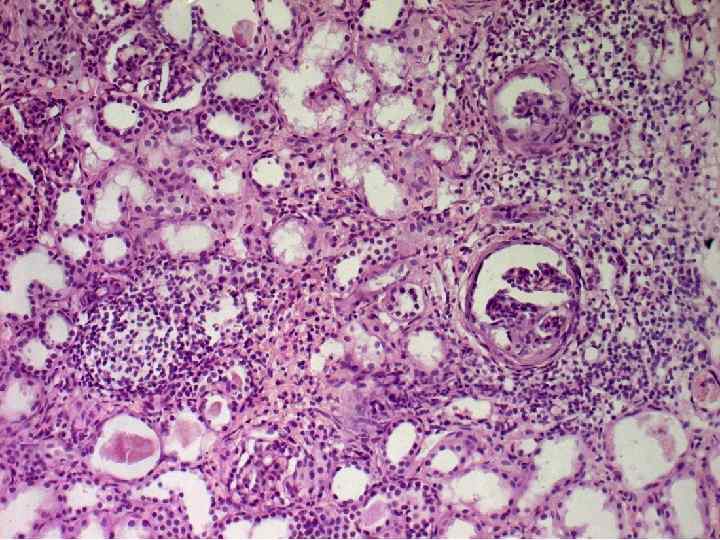

острый пиелоне фрит Гнойное воспаление с абцедированием Хронический пиелонефрит Лимфогистиоцитарная инфильтрация и склероз стромы, Перигломерулярный склероз Кистозная атрофия канальцев «тиреодизация почки» Ассиметричное сморщивание почек с грубыми рубцами

Хронический пиелонефрит

13% случаев ХР. П не выявляют при жизни больных (у мужчин) 10% случаев ХР. П имеет место гипердиагностика (у женщин)